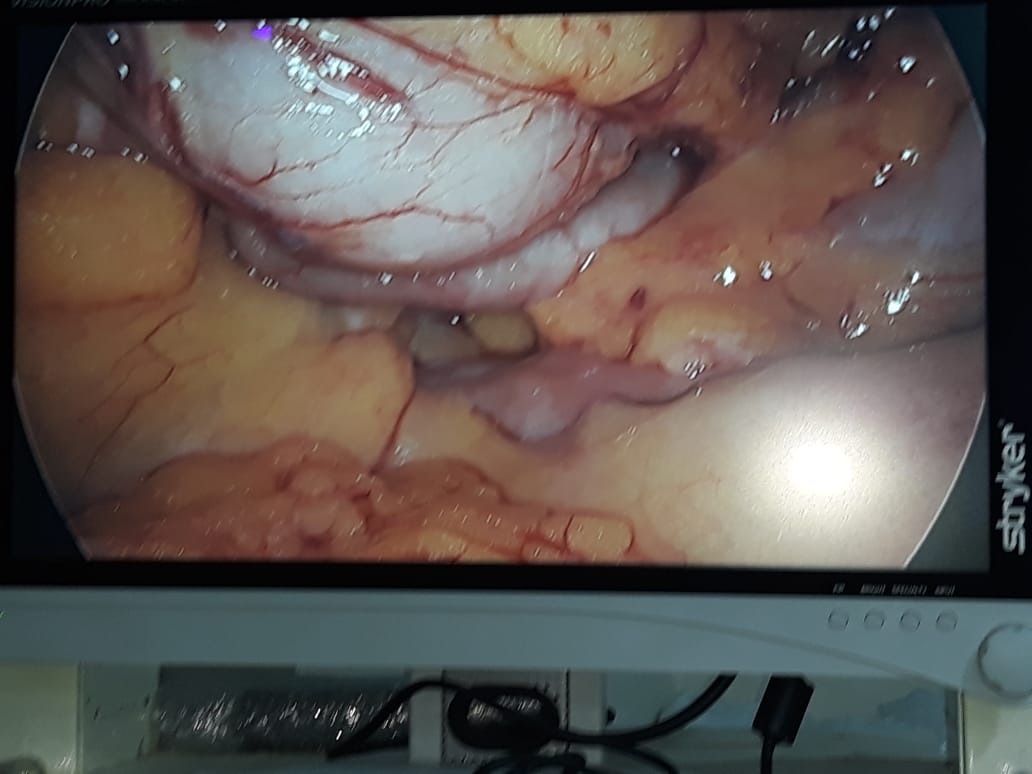

A Young lady who was a small kid...when her mother was operated for a Complex Gastrointestinal condition almost 14 years back by Dr Suddhasattwa Sen suddenly came in with severe blood loss from Gastrointestinal tract with a loss of almost 2 to 3 litres of blood with Shock with fainting . Further stabilisation was done and then extensive investigation revealed not only Piles and GI Ulcers but also SRUS Bleeding ulcers in rectum. A condition called Solitary Rectal Ulcer Syndrome ( a complex and difficult to cure anorectal problem ) . Her hemoglobin dropped to below 7 gm% She finally underwent surgery after 5 days and left home after 2 days post op without any further bleed or problems .